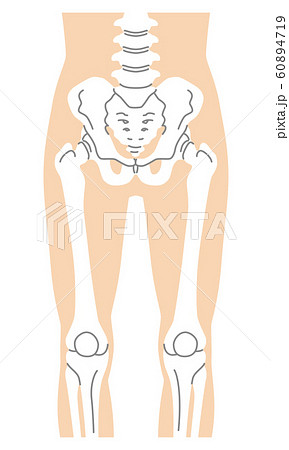

解剖学 12骨盤ってどんな骨 実際のスケッチと一緒に解説 ナツヲカケル 兼業クリエイター雑記

股関節 骨盤 大腿骨 膝蓋骨のイラスト素材

下半身 骨盤 大腿骨 膝蓋骨 人体解剖学 構造 の画像素材 イラスト素材ならイメージナビ

腸骨 仙骨 座骨を含めた骨盤周辺の骨のイラストのイラスト素材

下半身 大腿骨 膝蓋骨 脛骨 人体解剖学 構造 の画像素材 イラスト素材ならイメージナビ

股関節 骨盤 大腿骨 膝蓋骨のイラスト素材

下半身 大腿骨 膝蓋骨 脛骨 人体解剖学 構造 の画像素材 イラスト素材ならイメージナビ

骨盤と大腿骨のイラスト素材

下半身 大腿骨 膝蓋骨 脛骨 人体解剖学 構造 の画像素材 イラスト素材ならイメージナビ

股関節 骨盤 大腿骨 膝蓋骨のイラスト素材

下半身 大腿骨 膝蓋骨 脛骨 人体解剖学 構造 の画像素材 イラスト素材ならイメージナビ